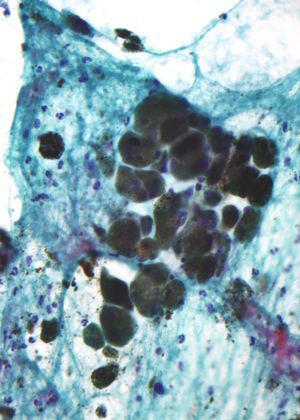

صبغة الميلانين (مادة حبيبية تعكس الضوء-وسط الصورة) في ورم ميلانيني مصبوغ.